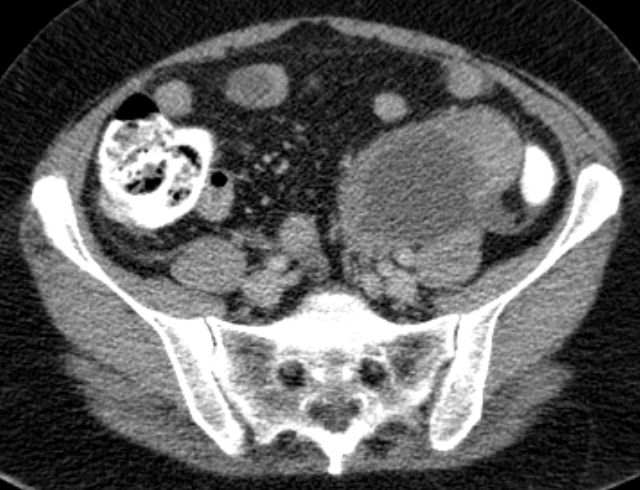

malignes Teratom 58-jährige Frau mit einen malignen Teratom mit Abszedierung und akuter Peritonitis.

Tumormarker AFP 2,86; CEA 2,27; CA 19.9 = 33 060 (N < 37!)

Makroskopie: Mehrteilige, maximal 10,9 cm messende, knotige, gelblichbräunliche und z. T. bröckelig zerfallende Gewebeproben.